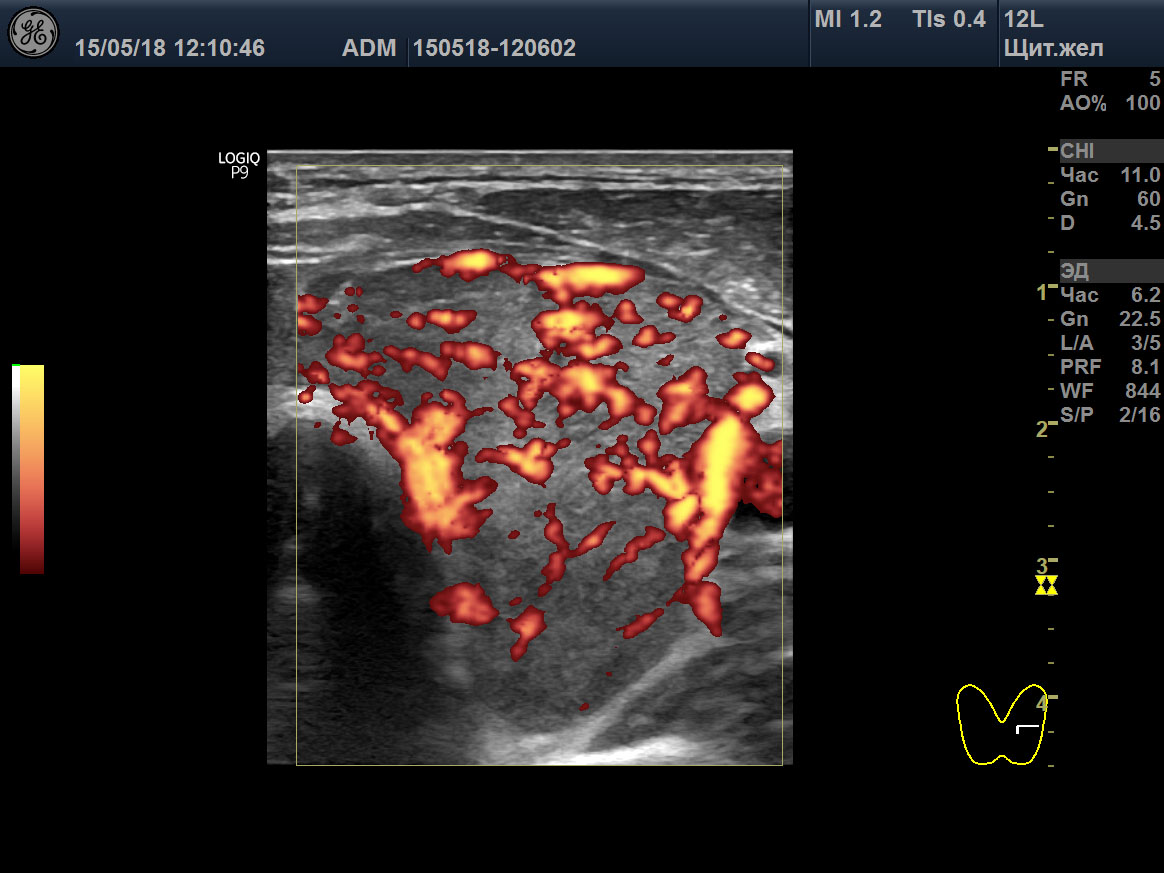

15 мая 2018 ультразвуковое исследование (УЗИ) щитовидной железы выявило зоб 3 степени (объём 45 мл; 23,6D + 21,4S), признаки умеренного отёка стромы (гомогенная гипоэхогенность паренхимы), значительное усиление интенсивности кровотока, систолическую пиковую скорость (SPV) кровотока в системе верхних щитовидных артериях (STA) 123 cm/sec справа и 160 cm/sec слева (рисунок: A, B, C).

A

B

C

D

E

F

Изображения щитовидной железы пациента в режиме Допплера. A, B, C ― до лечения (15 мая 2018), и D, E, F после лечения (23 августа 2021). A, D ― поперечная проекция левой доли. B, E ― продольная проекция левой доли. C, F ― SPV STA слева.